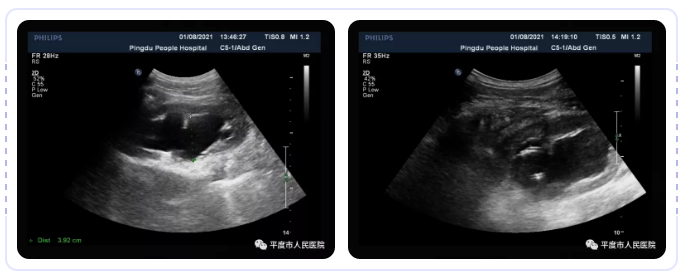

近日,我院超声科成功为几位肾积水病人进行了超声引导下肾穿刺造瘘引流手术,几例患者肾积水均为2公分以上,均为输尿管梗阻引起,梗阻原因为结石或肿瘤。

术中对穿刺点局部麻醉后,在超声引导下用8F猪尾巴引流管准确刺入右肾积水内,引流出浑浊尿液,引流通畅,穿刺过程都是在超声实时监护中,术后患者在泌尿外科配合进行抗感染治疗,疗效显著。本手术体现了精准医疗的理念,安全、创伤小,创口仅为2.7毫米,并发症少,费用低廉。